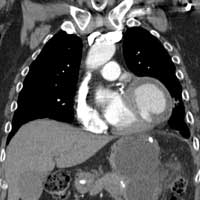

| Figure 1 & 2. Preoperative CT-scan | |

We report a case of a 78 y/o male with history of CAD, for which he underwent coronary artery by-pass surgery in 2004. The patient was admitted to the hospital with symptoms of moderate congestive heart failure. EKG showed no signs of acute ischemia and cardiac enzymes were negative. Cardiac ECHO showed a 6.8 x 5 cm pseudoaneurysm of the posterior left ventricle, well preserved ventricular function and no abnormalities of the mitral and aortic valves. Coronary angiogram demonstrated patency of all previous bypasses. The chest CT allowed better definition of the anatomy of the condition (Figure 1, 2). The procedure was performed through an antero-lateral left thoracotomy positioning the patient in a right lateral decubitus. The chest was entered at the 5th intercostal space and the sterno-costal junction was interrupted to optimize exposure. The left lung was displaced posteriorly and the pericardium was opened longitudinally and posteriorly to the phrenic nerve. Dissection of the heart surface from the pericardium was easily completed obtaining perfect exposure of the left ventricular pseudo-aneurysm. The previous by-pass grafts were never visualized, being distant from the operative field. Cardiopulmonary bypass was established through the left femoral vessels using a 17 F arterial femoral cannula and a 25 F multistage venous femoral cannula. The left ventricle was vented through the apex using a 10 F suction catheter. Systemic pressure was kept above 70 mmHg and the heart was decompressed before entering the left ventricular cavity via a longitudinal incision through the wall of the pseudoaneurysm (Figure 3). A bovine patch pericardial repair was completed with interrupted pledgetted sutures maintaining the architecture of the left ventricle (Figure 4). The closure was reinforced overlapping the wall of the pseudoaneurysm over the patch closure (Figure 5). Meticulous de-airing was completed under TTE monitoring before allowing ejection of the left ventricle into the circulation. De-airing was accomplished placing the patient in steep Trendelemburg position and maintaining full suction on the apical vent. Cardioplulmonary bypass was weaned-off without complications. The patient postoperative course was uncomplicated and he was discharged home in postoperative day 6. The postoperative CT-scan image is shown (Figure 6).